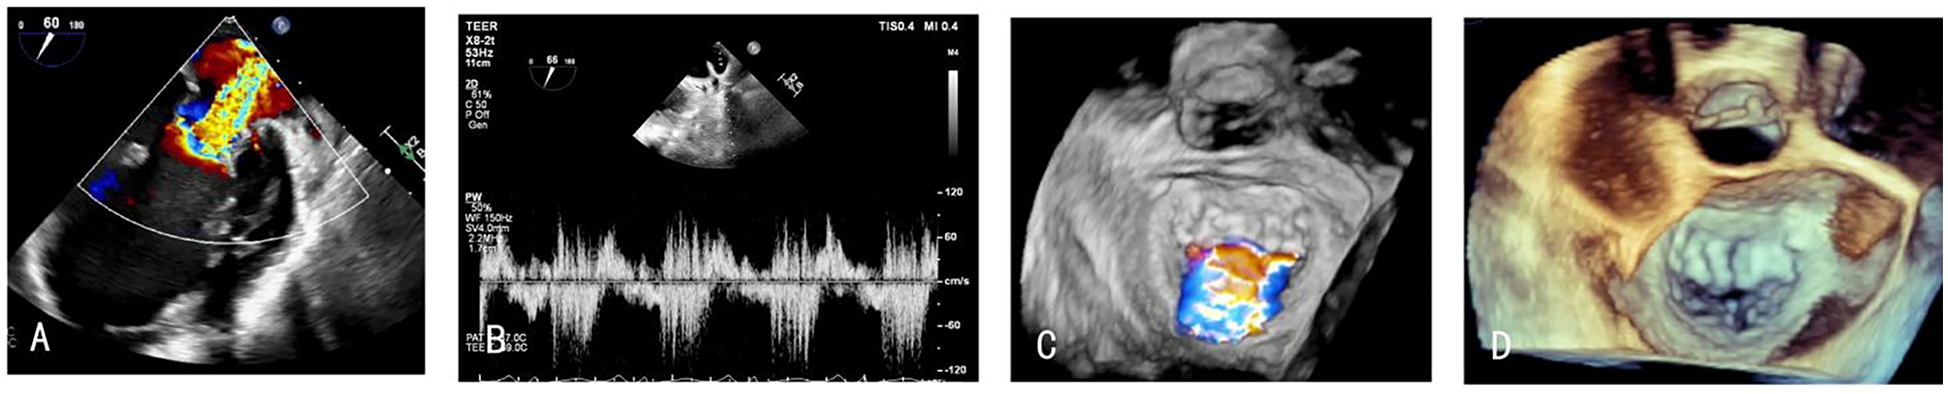

Figure 2

(A,C,D) TEE showing the MR between A2 and P2, (B) pulmonary vein systolic flow reversal before the procedure.